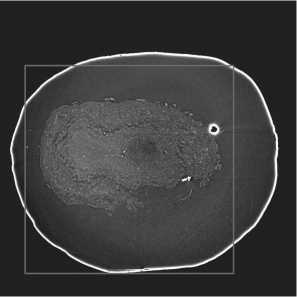

To decrease computational complexity and training time, expert-defined 864 X 864 regions of interest (ROIs) were extracted from each slice and used for model learning. An example of a slice with overlaid ROI is demonstrated in fig. 2 b .

Fig. 2. Visualization: (a) 3D-volume of the OB from 300 consecutive slices; (b) OB slice with overlaid 864 X 864 ROI boundaries (purple)